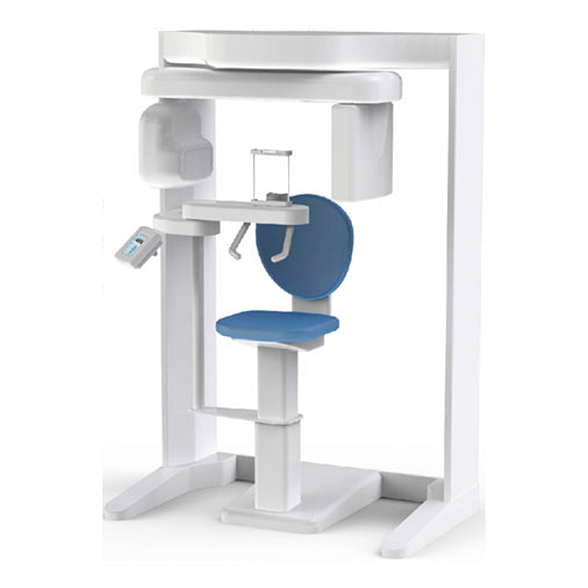

Fona XPan 3D - рентгенографическая цифровая система панорамной съемки

Fona XPan 3D: Цифровая рентгенографическая система для точной диагностики

Система Fona XPan 3D представляет собой современное решение для панорамной и 3D-визуализации в стоматологической практике. Это оборудование нового поколения, которое объединяет в себе проверенную надежность панорамной съемки и передовые возможности трехмерной томографии. Система создана для того, чтобы предоставить врачу-стоматологу, ортодонту или челюстно-лицевому хирургу максимально полную диагностическую информацию для постановки точного диагноза и планирования эффективного лечения.

Fona XPan 3D — это инвестиция в качество диагностики и безопасность пациентов. Система позволяет за одно сканирование получить как обзорный панорамный снимок, так и прицельные 3D-томограммы интересующей области, минимизируя лучевую нагрузку и экономя время врача и пациента.

- Эффективность работы: Быстрое сканирование (часто всего за 10-20 секунд) и мгновенная передача данных на компьютер врача ускоряют процесс приема и повышают пропускную способность кабинета.

- Удобство для пациента: Компактная конструкция, комфортная фиксация головы и короткое время процедуры делают обследование простым и не вызывающим дискомфорта, что особенно важно для детей и пожилых людей.

| Габариты аппарата (приблизительно) | Высота: ~180-200 см, Ширина: ~150-170 см, Глубина: ~120-150 см |

| Электропитание | 220В / 50-60 Гц |

Требуется ли специальное помещение?

Да, для установки необходимо помещение, отвечающее требованиям к рентген-кабинетам: соответствующая площадь, защитное покрытие стен (при необходимости), система вентиляции. Наши специалисты помогут вам с подготовкой технического задания для ремонта.